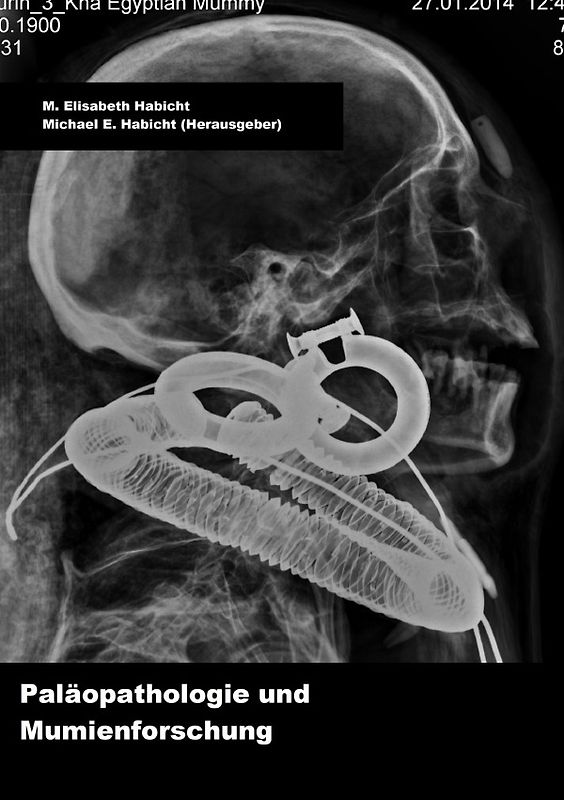

Handbuch Paläopathologie und Mumienforschung

Michael E. Habicht (Broschiert, Deutsch)

Das Handbuch soll dem Anfänger wichtige Informationen zur Bearbeitung und Beprobung von Mumien bieten und stellt wichtige Formeln und anthropologische Messpunkte für den Einsatz im Feld in übersichtlicher Weise zusammen. Zudem sind Literaturhinweise für Paläopathologien nach Diagnosen geordnet zusammengestellt. INHALT Kapitel 1: Archäologische Erfassung und Bergung von Material für genetische Beprobung Kapitel 2: Anthropologische Vermessung, Körpergrösse Kapitel 3: Archäologische Auswertung Kapitel 4: Röntgen Kapitel 5: Forensische Gesichtsrekonstruktion Kapitel 6: Paläopathologische Diagnosen Kapitel 7: Radiokarbondatierung und WAXS-Datierung Kapitel 8: Chronologie Kapitel 9: Risikomanagement Literatur und Internetlinks zu archäologischen Journalen 156 Seiten, zahlreiche Abbildungen, 3. aktualisierte Auflage